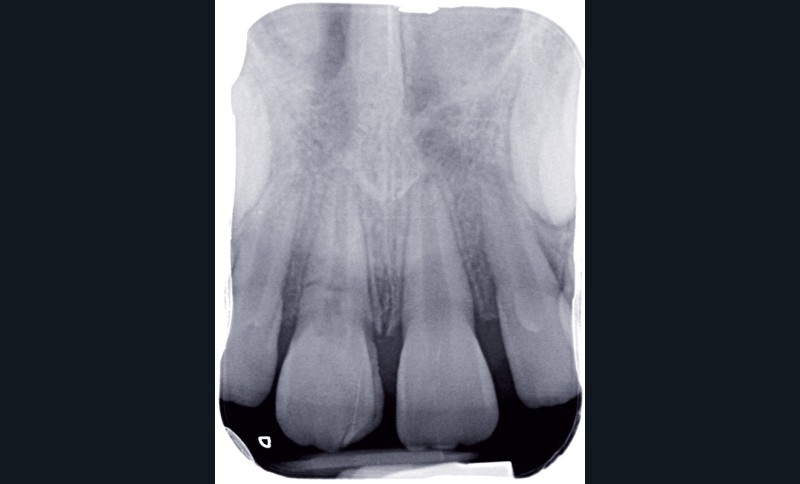

a à d Jeune patiente âgée de 8 ans, adressée suite à un traumatisme survenu 3 semaines auparavant, pour l’extraction de sa 21. La vue clinique montre un saignement ligamentaire, une mobilité coronaire et une fracture coronaire amélodentinaire longitudinale partant de l’angle mésial et se poursuivant en direction radiculaire sous-gingivale (a). Un test de vitalité positif indique que la dent est vitale, la radiographie permet de poser le diagnostic de fracture coronoradiculaire, et d’objectiver l’immaturité radiculaire (stade 8 de Nolla) (b). Une contention est mise en place et la plaie dentinaire coronaire est scellée au mieux par collage afin de limiter le risque d’une complication infectieuse (c). A 15 jours la dent est vivante et aucune complication n’est apparue (d). La patiente est revue après 3 mois pour déposer la contention, le test de vitalité est positif, et la radiographie de contrôle montre une apexogenèse en cours (e). Cependant la gencive s’est invaginée dans le trait de fracture (f). La zone est débridée sous microscope (g) puis scellée et reconstituée à l’aide d’un adhésif SAM et d’un composite fluide (h). Le contrôle radiographique à 6 mois est satisfaisant (i). Ce cas clinique illustre le fort potentiel des pulpes jeunes et du ligament alvéolodentaire à résister aux agressions et à assurer les fonctions dentinogénétiques et l’édification radiculaire.